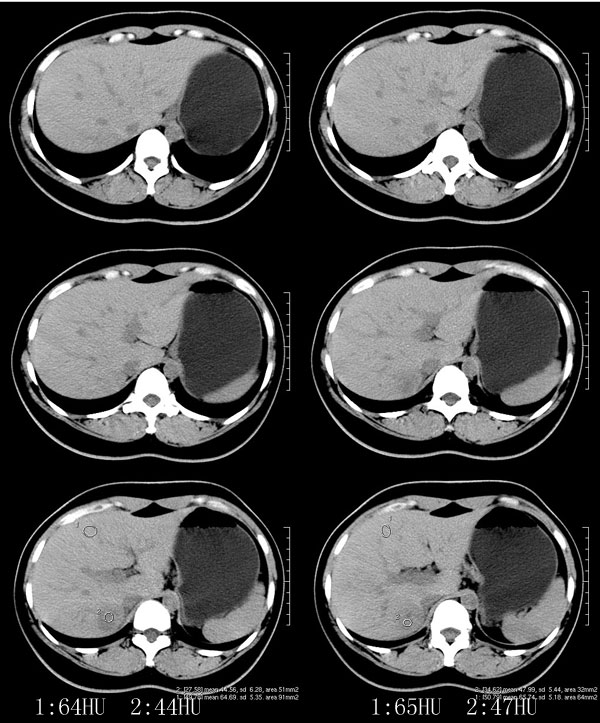

以下是引用52yingxiang在2007-9-16 10:16:00的发言:[br]肝脏局灶性结节增生影象表现(fnh)[br][br]肝脏局灶性结节增生是一种少见的肝脏良性肿瘤,可表现为边界清楚并无包膜的实质性肿块。病变大小不一,多系单发,亦可多发。组织学上是由结构紊乱的肝细胞、库普弗细胞、胆管、血管和粗厚的纤维性间隔所组成。[br]局灶性结节增生的ct表现可归纳为6点:[br]1、密度变化是其特征性改变,平扫多为低密度,少数为等密度,无论增强的早期或晚期均可能呈等密度,增强扫描有助于发现平扫为等密度的病灶;[br]2、中心疤痕,部分病灶在动态ct扫描时早期可看到中心疤痕增生性结节性病灶,ct血管造影也可看到普通ct不能显示的车轮状血管和车轴样改变;[br]3、纤维性分隔影,平扫为低密度,增强后为高密度;[br]4、包膜征象,增强后可以出现包膜强化,晚期较明显;[br]5、邻近血管的改变,主要是肝静脉受压,是发现等密度病变的重要依据;[br]6、瘤内胆管显影,这需要在胆管造影增强的情况下方能显示,出现率不高。[br][br]本例特点: 平扫低密度,增强动脉期明显强化,中心点条状低密度影(考虑纤维瘢痕),静脉期及延时期明显退减并与肝呈等密度,但中心仍可见低密度灶。[br]考虑肝脏局灶性结节增生(fnh)